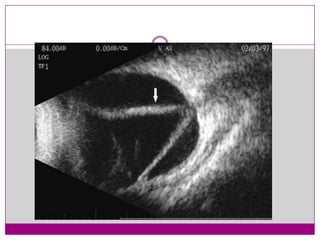

3 B-scan ultrasonography shows good mobility of

the retina and vitreous